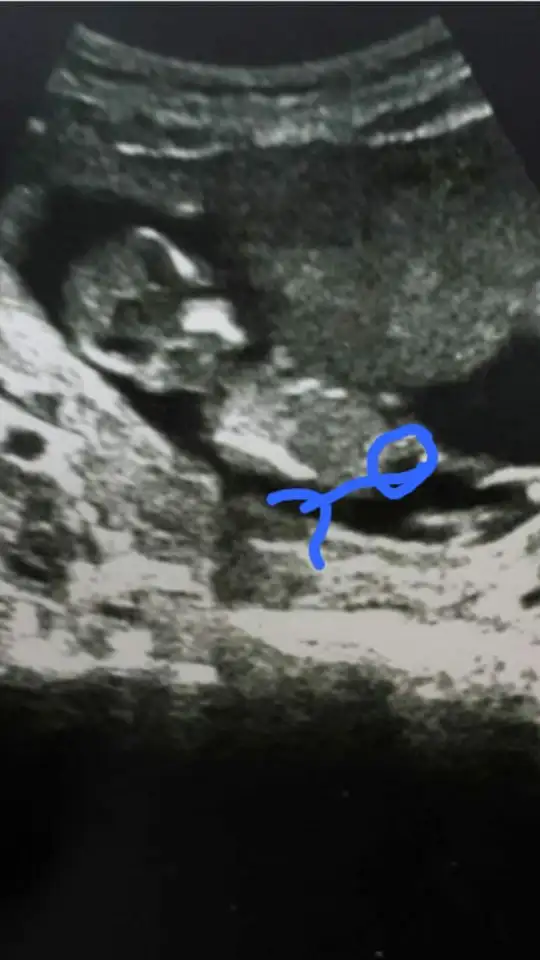

Evet pipi oldugu halde dr pipi olsa söylemezmi demiştin M mely15 de çizdiğim görüntüye pipi o dedi ama senin istegini kıramadım .ama sonuç mutlusunuz hepsi evlat yeterki saglıklı hayırlı olsun 😊

Evet canım pipi yi çizdin sen daha yapcan maşallah sana 👍saglık la gelsin oğlunuz S seymayaz